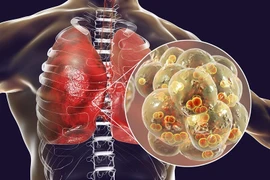

(khoahocdoisong.vn) - Có rất nhiều yếu tố gây các bệnh lý đường hô hấp, đặc biệt là những tác nhân virus, vi khuẩn. Ngoài ra, các yếu tố khác như thuốc lá, ô nhiễm không khí, di truyền...

Các trường hợp viêm phổi nặng do vi khuẩn kháng thuốc thường kéo dài, cần đến các loại kháng sinh mạnh và đắt tiền, đôi khi phải dùng nhiều loại thuốc kết hợp.